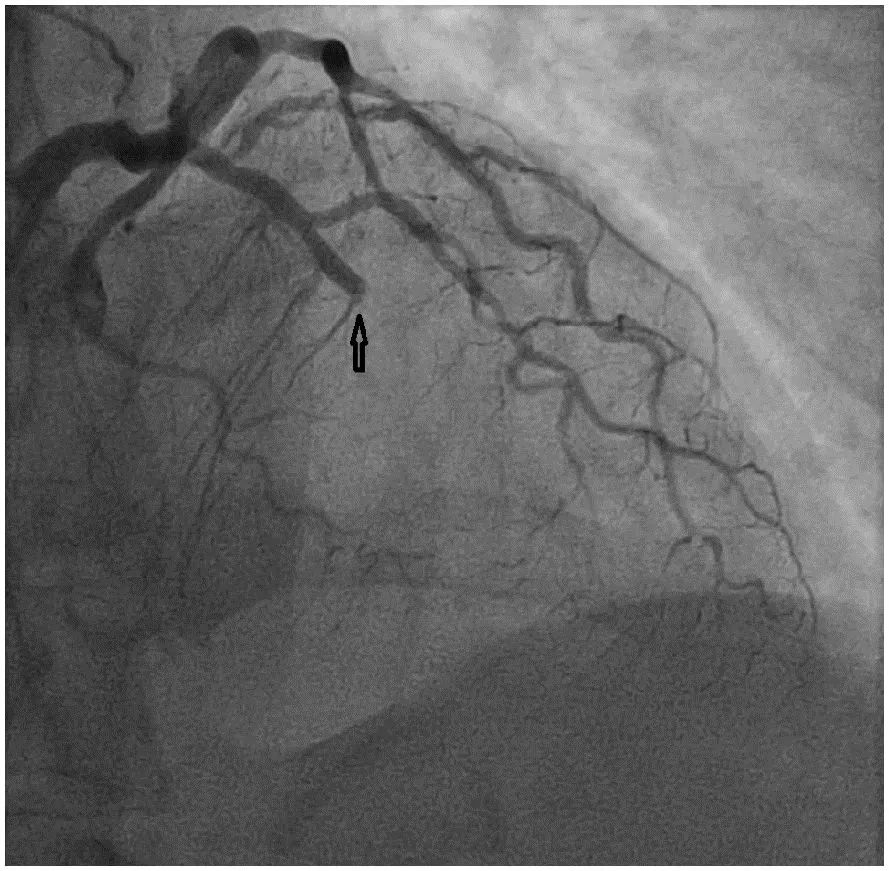

心电图显示前外侧壁导联ST段抬高和QS波。紧急冠状动脉造影显示左前降支(LAD)中段闭塞达100%(图1)。通过PCI治疗成功放置两个药物洗脱支架后,TIMI 2级血流。超声心动图显示左室射血分数为25%,可能存在左室附壁血栓,需要全身抗凝。6天后,患者病情稳定后出院。

图1 左冠状动脉造影显示100%左中前降支动脉闭塞